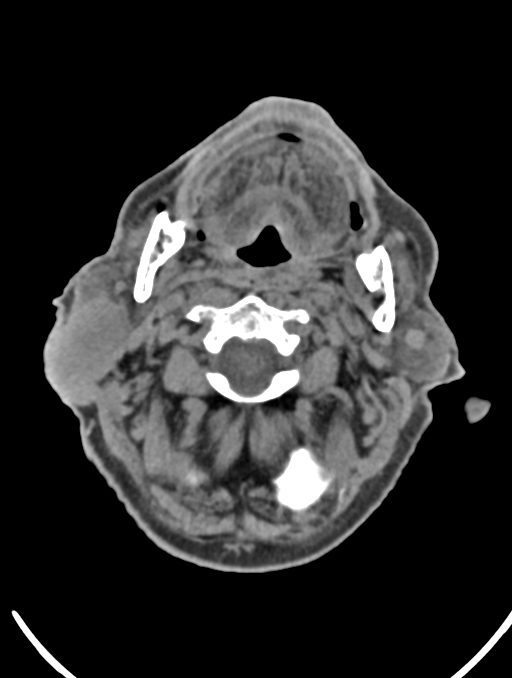

در سی تی اسکن ادنوم پاروتید، دستگاه تصاویری عرضی مقطع ایی از گوش در ناحیه سر و صروت ایجاد می کند. این تصویربرداری از اشعه ایکس برای ایجاد تصویر استفاده می کند.

در سي تي اسکن اسپيرال نازو فارنکس با و بدون کنتراست (مولتي ديدکتور 16 با مقاطع ظريف و بازسازي هاي ساژيتال و کرونال):

– توده نسج نرمي به ابعاد mm 40 x 45 x 60 در ناحيه پاروتيد راست، با enhancement هتروژن پس از تزريق کنتراست مشهود است که مطرح کننده آدنوم پاروتيد مي باشد.

– شواهدي از تهاجم توده به استخوان و عروق اطراف مشهود نيست .

– کلسيفيکاسيون در ديواره شريان هاي کاروتيد دو طرف مشهود است .